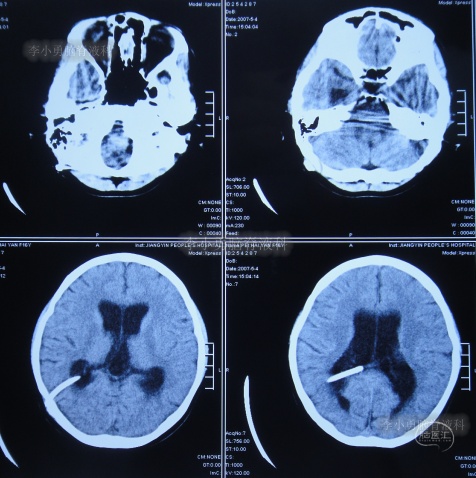

于入院后2019年12月30日,进行了第3次进行了脑室腹腔分流术(分流阀初始压力2.0),仍保留了原2根脑室分流管;术后当天查头颅CT示脑室仍有扩张,脑室内有3根管(图-9)。

图-9:2019年12月30日头颅CT

第3次脑室腹腔分流术后1个月即2020年2月初,再次出现记忆力减退视物模糊,再过1个月仍无任何改善,于2020年3月17日(第3次脑室腹腔分流术后2个半月),到江苏省江阴某医院检查了头颅CT示脑室仍扩张(图-10)。

图-10:2020年3月17日头颅CT

2020年4月5日(第1次调压后18天),因症状持续不见减轻,到江苏省江阴某医院查头颅CT示脑室仍扩张(图-11)。

图-11:2020年4月5日头颅CT

但第2次调压仅2天后,症状又加重,到江苏省江阴某医院查头颅CT示脑室仍扩张(图-12)。为求进一步有效治疗,通过网络找到北京的李小勇脑脊液科。

图-12:2020年4月9日头颅CT